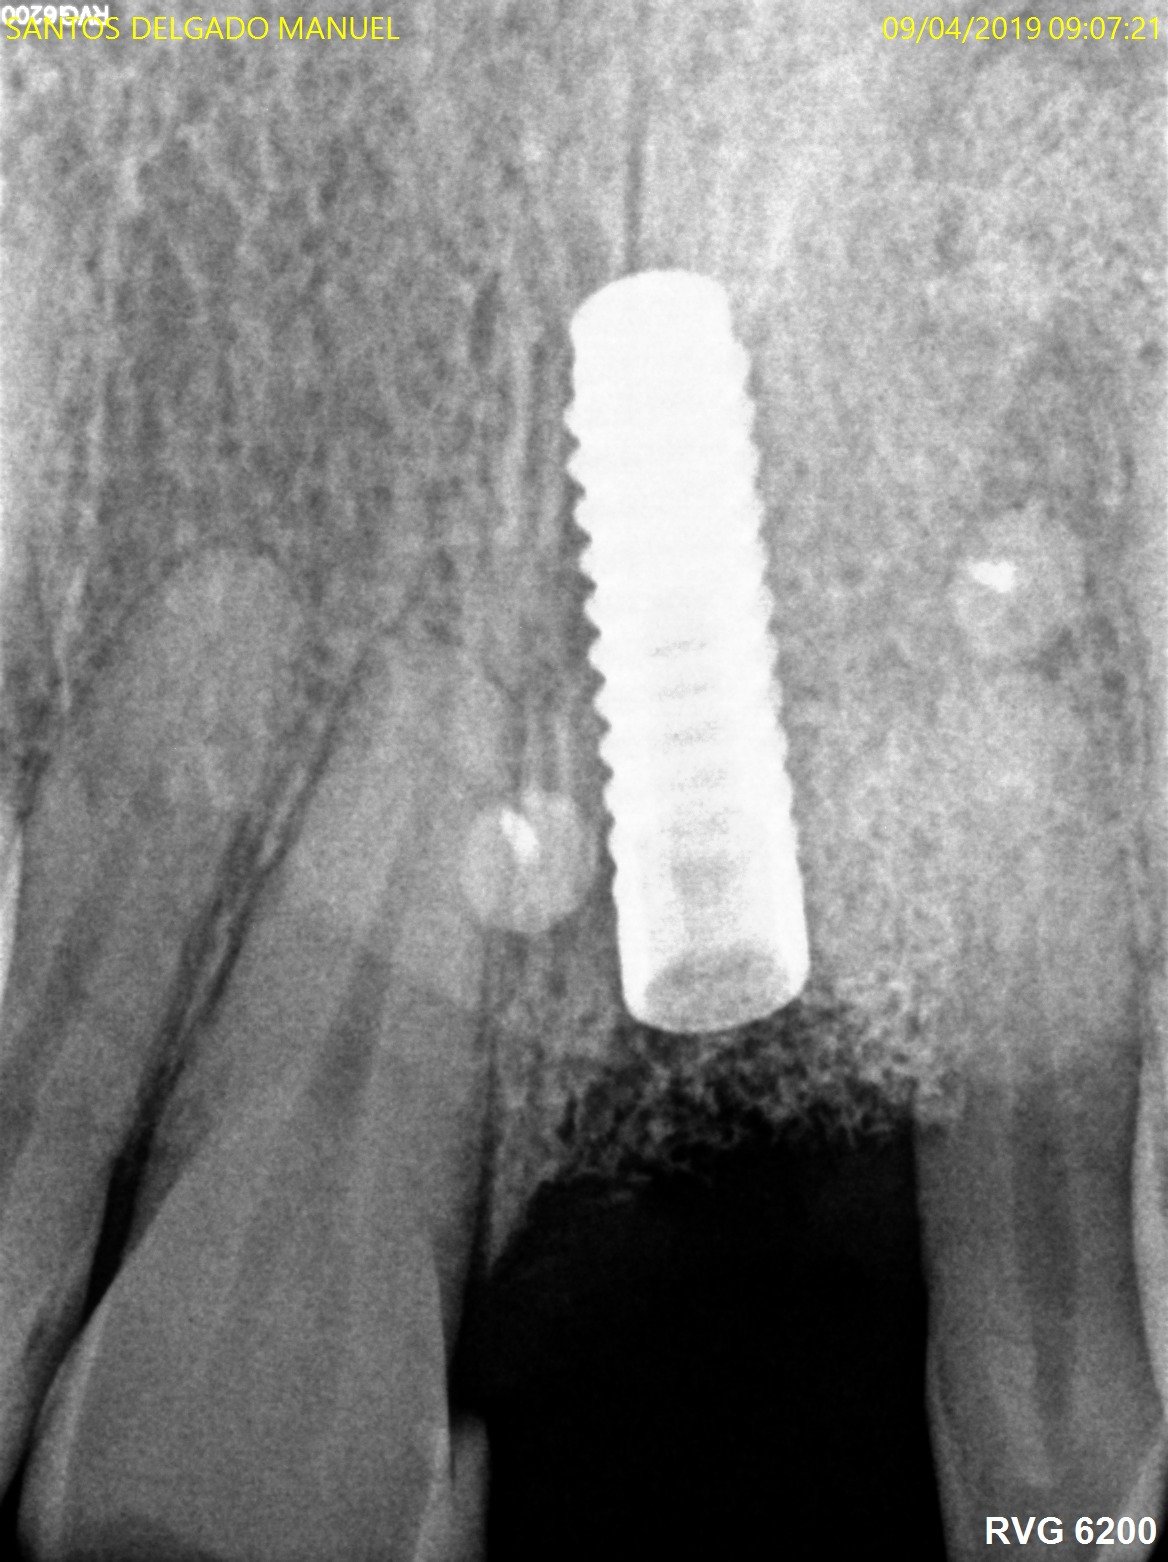

Marca del implante

Paciente de unos 40 años que hace 10 se puso este implante por un alumno de máster de implantes. Nunca ha estado cargado. No estamos seguros de que marca de [...]